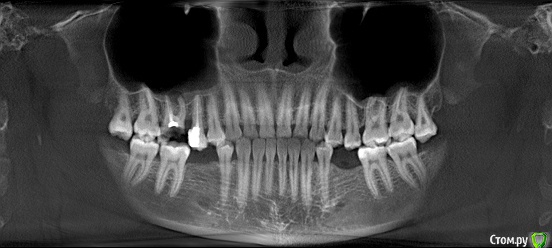

marilinka Опубликовано 26 мая, 2015 Поделиться Опубликовано 26 мая, 2015 Добрый день! Уважаемые стоматологи!Есть у меня один очень не хороший зуб, который хотелось бы сохранить, один стоматолог сразу сказал удалять....но у меня нет лишних зубов, 2 коренных зубов нет, они просто не выросли, зачатков тоже нет, после родов, очень испортились остальные, почти все жевательные зубы в пломбах, поэтому для меня это не просто прихоть, а действительно необходимость. Второй стоматолог сделав снимки и посмотрев зуб, дал 10 процентов....что скажете Вы стоит ли за него браться? Мне не жалко времени и денег, мне просто очень нужен зуб, пусть он хоть 5 лет простоит, но будет свой.Зуб 16, если правильно понимаю, пломба и часть зуба разрушены, под зубом киста, зуб абсолютно не беспокоит иногда воспаляется свищ.Как смогла сохранила фото с рентгена.Заранее спасибо за помощь! Ссылка на комментарий

marilinka Опубликовано 26 мая, 2015 Автор Поделиться Опубликовано 26 мая, 2015 Что хирурги в городе говорят?одтн врач сходу сказал удалятьвторой дал 10 процентов на хороший результат, сначала как поняла на долго лекарство для удаления кисты, переделка каналов, потом работа ортодонта… если он еще возьмется, часть под самую десну отпала, но примерно половина зуба цела. Может посоветуете в Тагиле в области грамотных врачей, еще очень много хотелось бы сделать, планирую имплантацию нижних зубов. Ссылка на комментарий

Гарриевич Опубликовано 27 мая, 2015 Поделиться Опубликовано 27 мая, 2015 после того как уберут весь кариес нужно оценить оставшиеся ткани и если их достаточно, то перелечить и покрыть коронкой с предварительным восстановлением 1 Ссылка на комментарий